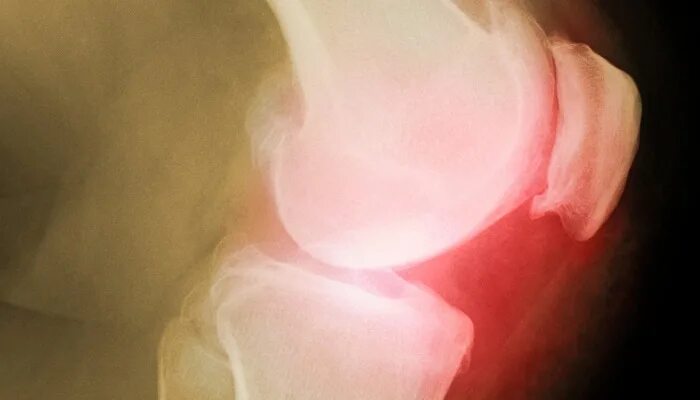

Болезнь соли в суставах